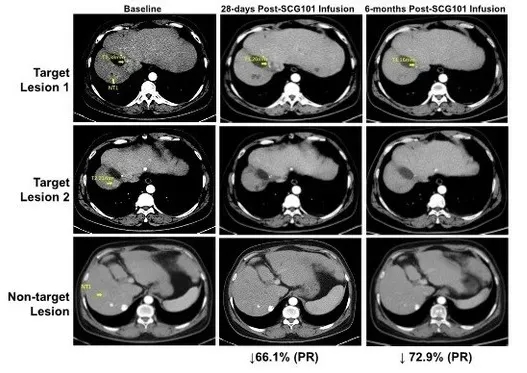

国际细胞与基因治疗大会(ISCT)上公布了SCG101治疗HBV相关肝细胞癌的振奋案例:患者治疗后达成部分缓解(PR),肿瘤缩小74.5%,乙肝感染实现100%清除。

具体来看,该患者接受单剂SCG101输注后,第28天靶病灶较基线缩小66%,达成部分缓解(PR);治疗第4个月,肿瘤进一步缩小至74.5%,另一处病灶完全消失(详见下图)。值得关注的是,试验期间患者未接受其他任何抗肿瘤治疗,截至数据统计时,肿瘤无进展时间已超6.9个月,持续维持缓解状态。

▲图源“SCG”,版权归原作者所有,如无意中侵犯了知识产权,请联系我们删除

此外,回输前后的肝脏免疫组化分析显示,乙肝表面抗原阳性肝细胞实现100%清除;HBV血清学标志HBsAg水平也显著下降,从输注前的557.96IU/mL降至输注后第7天的1.3IU/mL,第28天进一步降至0.08IU/mL(详见下图)。